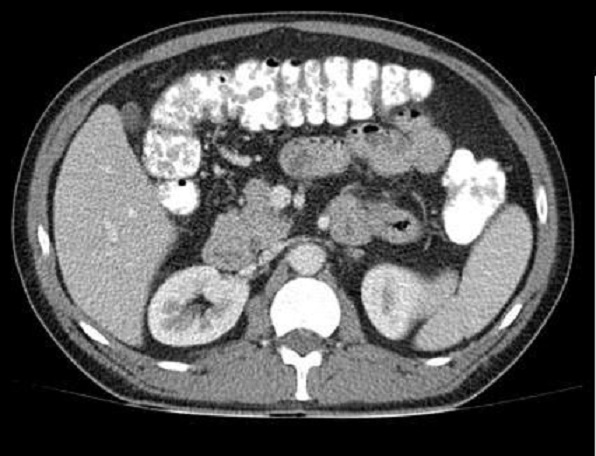

Image radiologique TDM

des

polyps du colon est aspect laculaire a sessile ou polypoide

a hyper-dense avec pedicule intra luminal du colon . Sa

nombreuse peut de quelque d'un au colon a multiple

polype s'etendre le long du colon .

Aspect du polyp

laculaire hyperdense a bord lisse et a sessile

rehaussement intraluminale du colon ( fleche blanche

) . Image TDM du polyp du colon ean coupe axiale . |

|

Polyp du colon sigmoide en

aspect laculaire a hyperdense situe intraluminale du colon . Sa bord est lisse et en sessile

. Image radiologique TDM en coupe axiale .a travers

S1, S2 . |